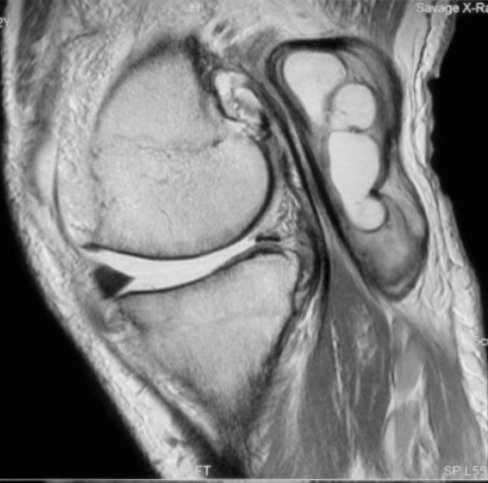

Heterogenous mass, low signal intensity T1, high signal intensity T2

- may have characteristic triple signal intensity

- area hyperintensity, isointensity and hypointensity

Knee

Heterogenous mass, not communicating with joint

DDx Baker's cyst

- semimembranosus

- communicates with joint

- between semimebranosus tendon and medial head gastrocnemius